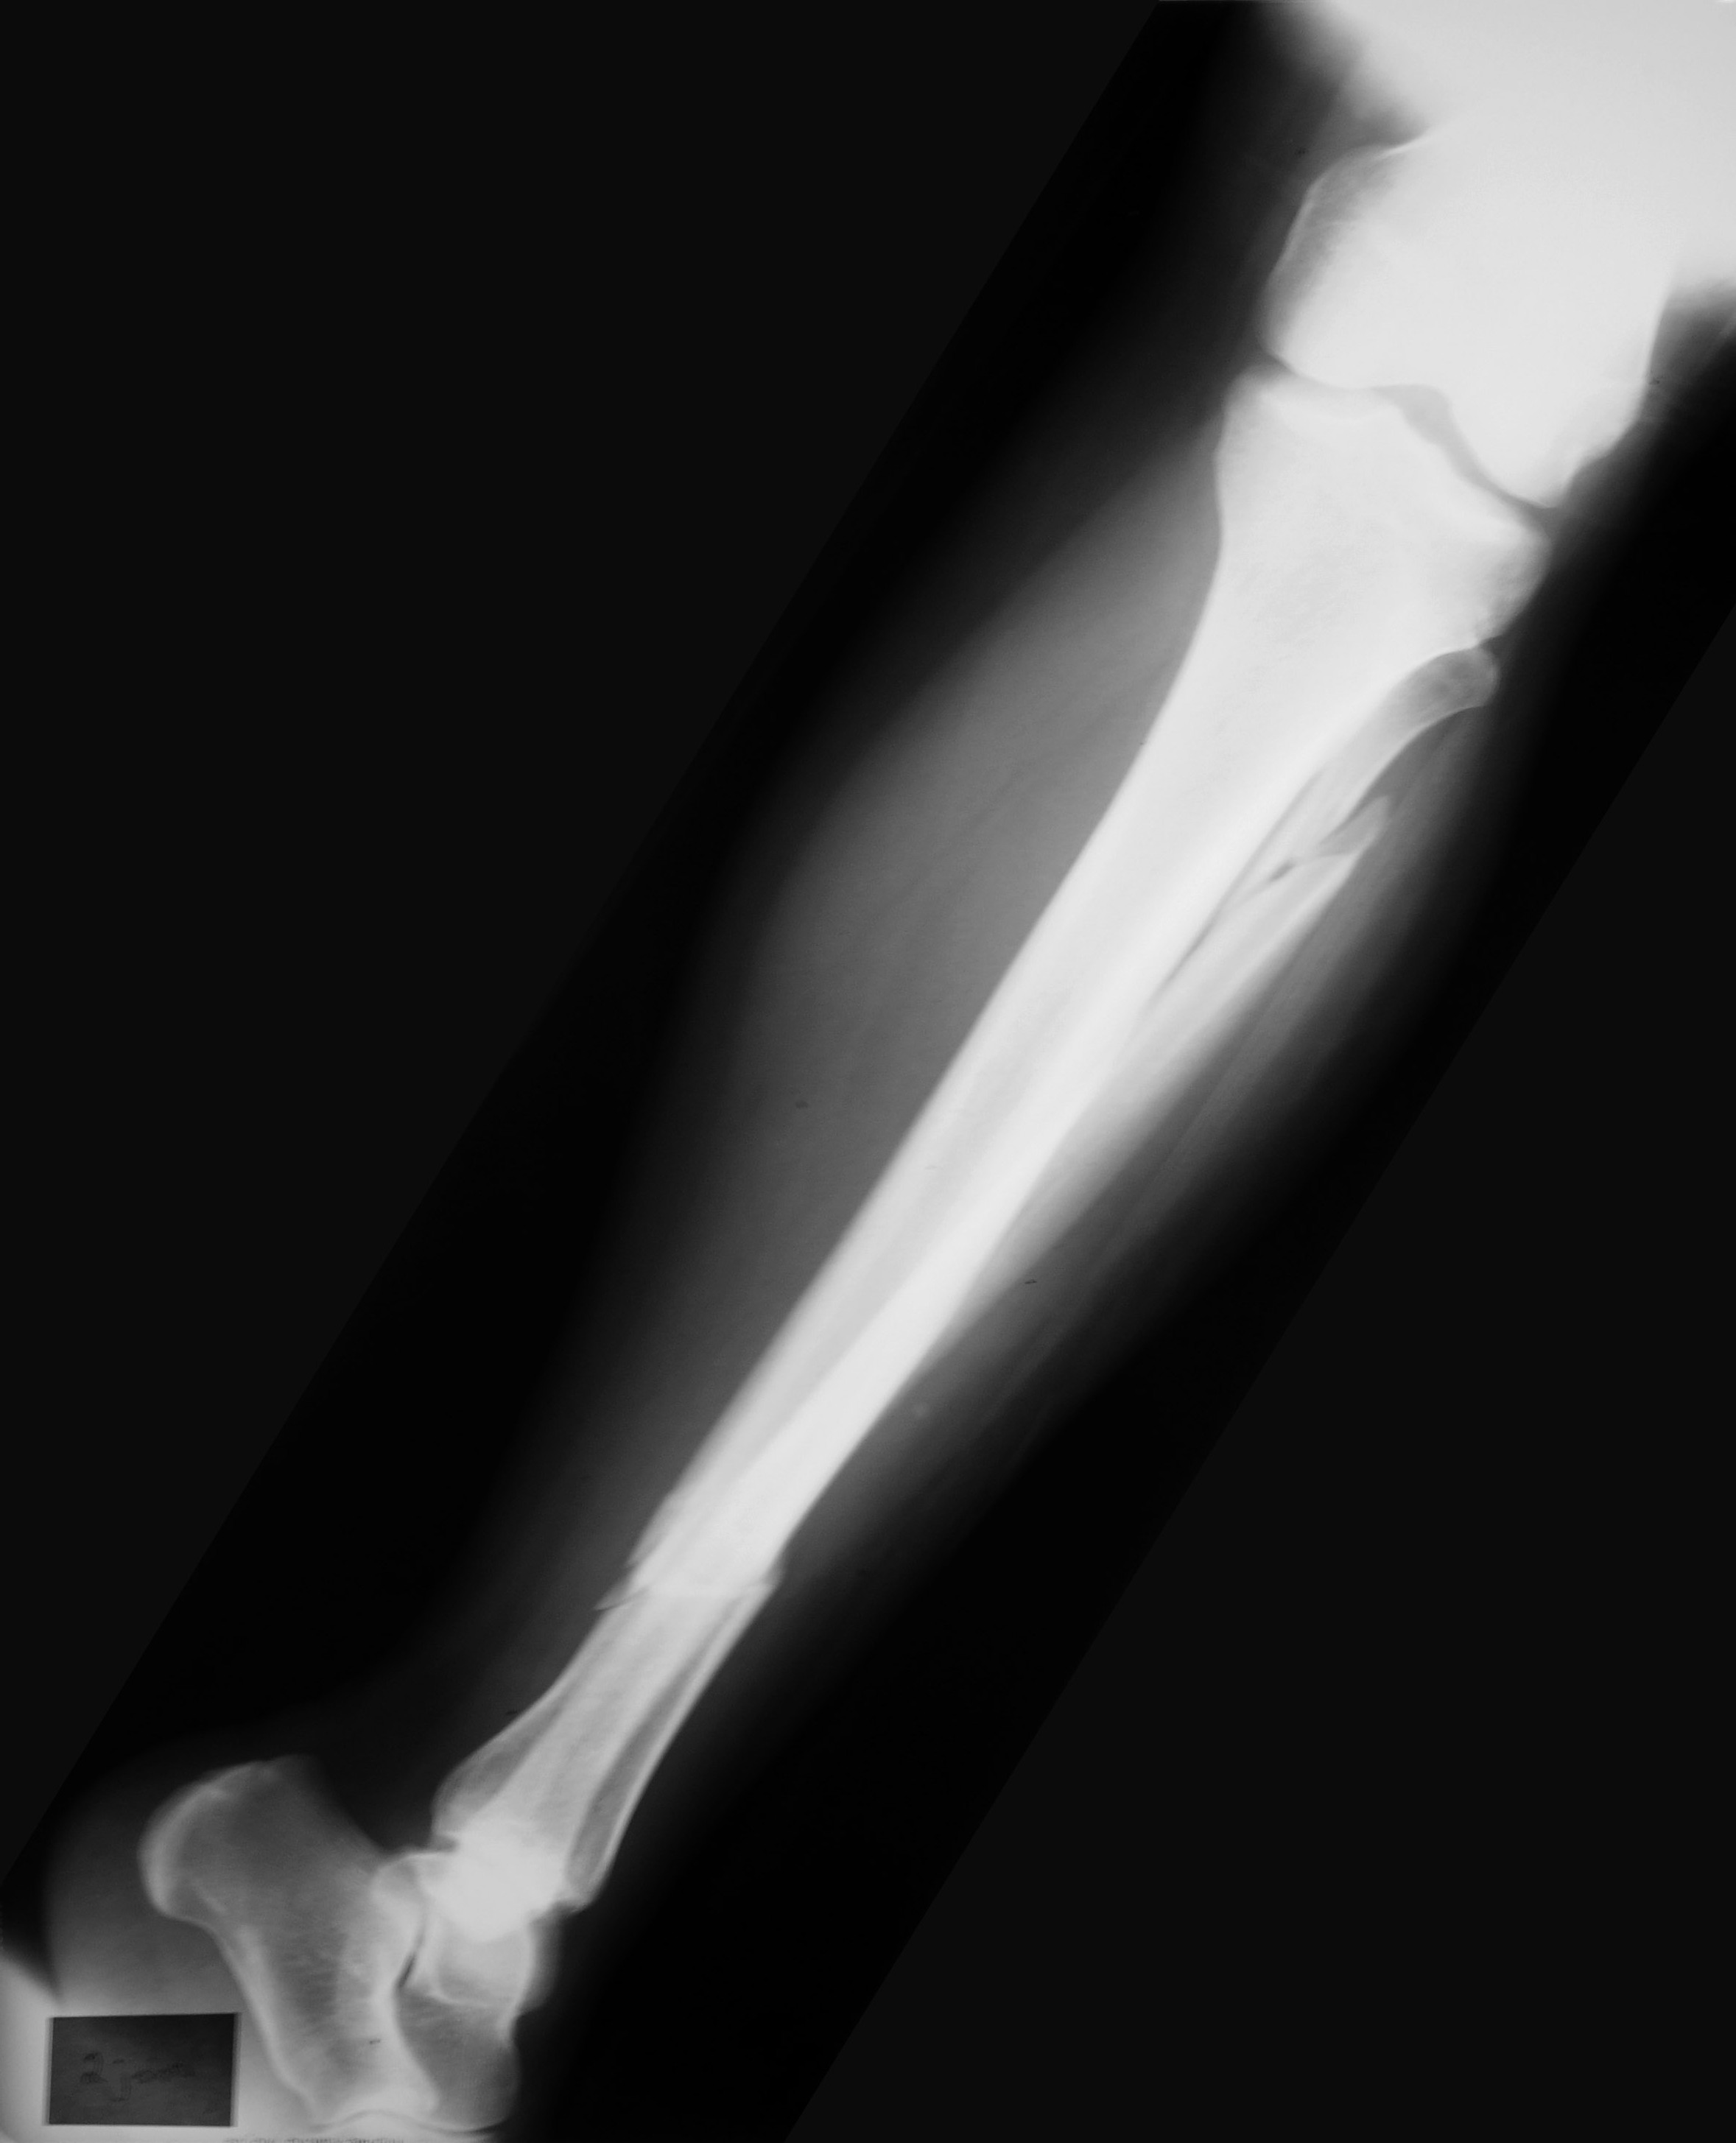

dsc_01592The bone mineral density tends to decrease drastically from the age of 50 years, especially with woman after menopause. This increases the risk of fractures in the hip etc.